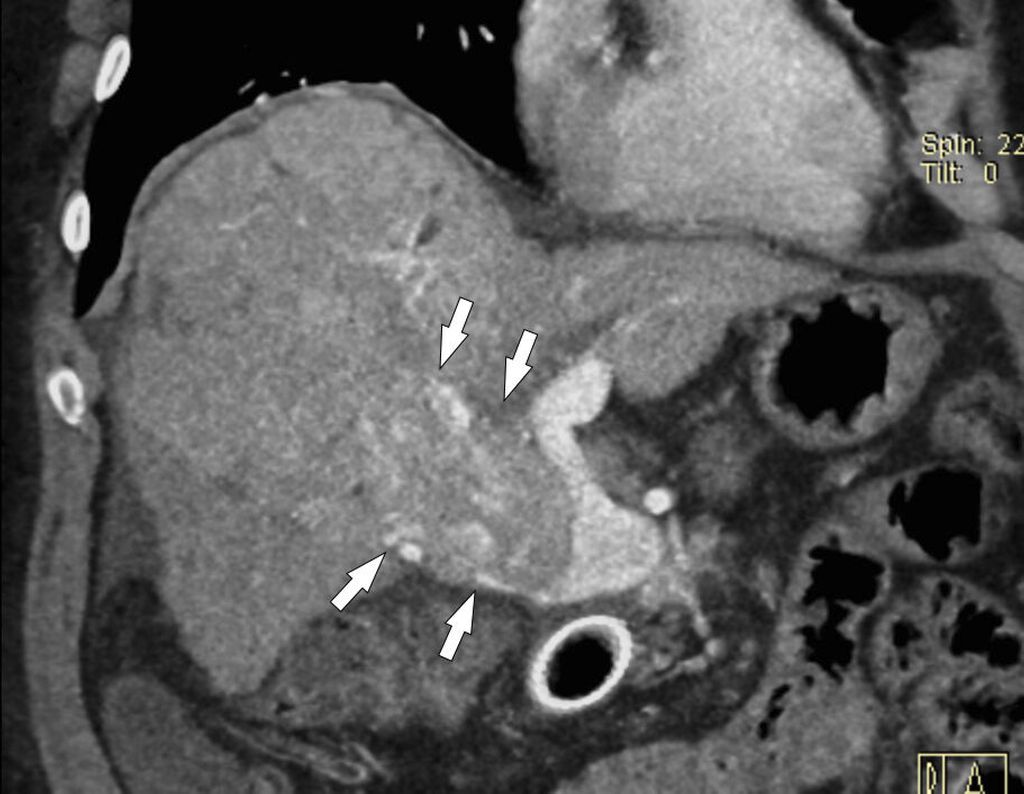

Die Häufigkeit eines hepatozellulären Karzinoms (HCC) ist wesentlich größer bei PVT-positiven als bei PVT-negativen Zirrhosepatienten (28,9% vs. 13,4%), was damit zusammenhängen mag, dass beide eher bei fortgeschrittener Zirrhose auftreten. Es ist essenziell, mittels Bildgebung nachzuweisen, dass der Pfortaderthrombus nicht mit dem HCC in Zusammenhang steht (Abb. 4). Ein HCC bei „blander“ Pfortaderthrombose ist in Abhängigkeit von Tumorstadium und Leberfunktion unter Umständen einer kurativen Behandlung (Resektion, interventionell-radiologische Tumorablation, Transplantation) zugänglich, während ein HCC mit „Tumorthrombus“ eine Kontraindikation für derartige Behandlungen darstellt.

Abb. 4: HCC und PVT: Das HCC im rechten Leberlappen (kleine Pfeile links) hat keinerlei Verbindung zum (blanden) Thrombus im Pfortaderhauptstamm, der kein Kontrastmittel aufnimmt (großer Pfeil)